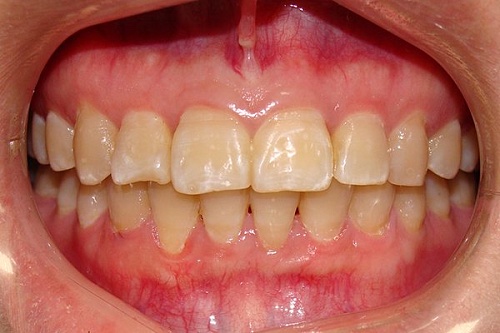

Изменения тканей, которые окружают корни зубов, к сожалению, неизбежны и с возрастом наблюдаются у всех, однако в разном объеме. Так, на развитие пародонтита влияет болезнетворная микрофлора полости рта, которая есть у каждого из нас, но на мы в силах повлиять на ее количество.

Сохранить зубы и пародонт помогает правильная гигиена полости рта дома и в кресле стоматолога, а также своевременное протезирование и имплантация, которые замещают удаленные зубы и равномерно распределяют жевательную нагрузку, не позволяя костной ткани атрофироваться.

Таким образом, по мнению стоматологов, риск возникновения болезней десен на 80% зависит от сознательности самого пациента.